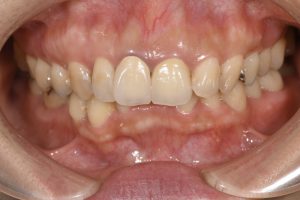

Before

術前

前歯2本がセラミックで治療されているが、右上1番にメタルの土台が使用されているため、歯茎が黒く見える、

また適合不良のため2本とも歯肉に炎症があり、歯肉が赤っぽくなっている。